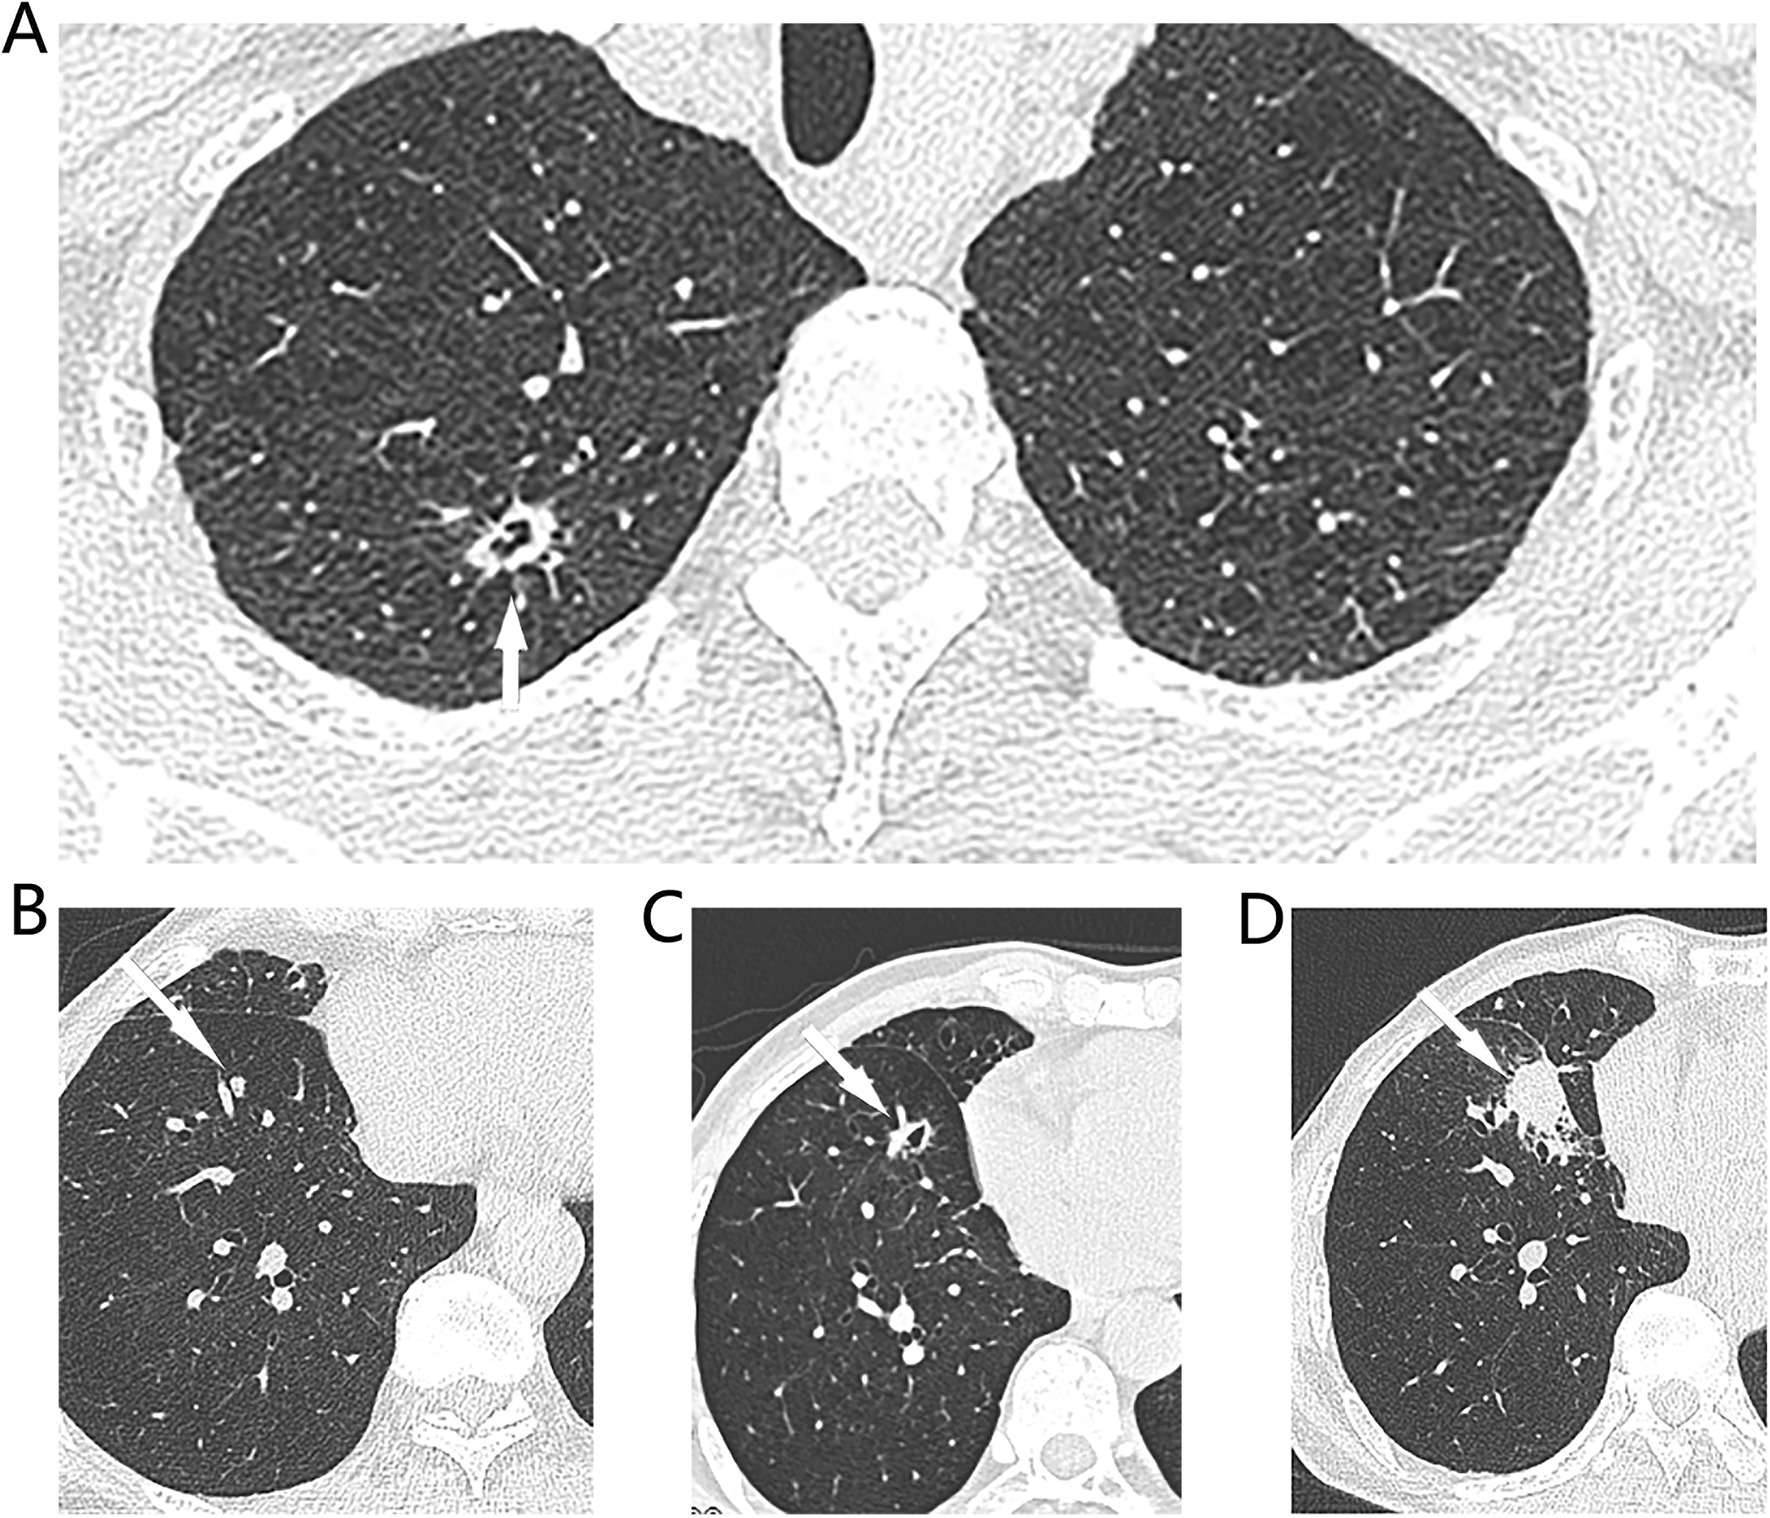

Overall, 94 patients with 125 non-dominant tumors suspected of being multiple primary lung cancers were followed-up for at least 6 months. Of these, 17 underwent follow-up CT for ≤ 365 days and 77 follow-up CT for > 365 days. The median follow-up time was 530 (416–585) days. Of these patients, 19 had 29 (29/125, 23.2%) small pulmonary nodules (≤ 6 mm) evidencing interval growth on follow-up CT (Additional file 1: Fig. S1, Additional file 2: Fig. S2) and 4 with 5 nodules underwent surgical resection; 3 were pathologically confirmed to have three multiple primary lung cancers; 1 had two pulmonary nodules that were metastases from colon cancer; and 1 was pathologically diagnosed with multiple primary lung cancer via CT-guided core needle biopsy (several N2 lymph nodes were cancer-positive). The other 14 patients were followed-up (Table 2). The medium volume doubling time was 347 (233–487.5) days. Figure 1 shows a patient with an multiple primary lung cancer and a 5-mm solid nodule in the right lower lobe that exhibited interval growth from 5 to 24 mm over 14 months, accompanied by multiple N2 mediastinal lymph node metastases. CT-guided core needle biopsy of the right lower lobe revealed an invasive adenocarcinoma. Comprehensive histological assessment diagnosed multiple primary lung cancers.

Fig. 1.

Typical CT images of synchronous multiple primary lung cancers. A On preoperative CT of a 67-year-old male patient shown a 13*8 mm cystic nodule (white arrow) in the right upper lobe, and B a 5 mm solid nodule (white arrow) in the S8 segment of right lower lobe. Patient received right upper lobectomy and systemic lymph node dissection in July 2019 and confirmed as adenocarcinomas (80% acinar adenocarcinoma, 10% solid adenocarcinoma) on surgical pathology, pT1bN0M0, IA2. The small solid indetermined nodule of the S8 segment of right lower lobe was followed up. C 5 months later, the nodule had grown up to a 10 mm cystic nodule. D 14 months later, this nodule had grown up to a 24*20 mm solid nodule and with multiple N2 lymph node enlargement, CT guided core needle biopsy shown acinar predominant adenocarninoma. This patient was diagnosed with synchronous multiple primary lung cancers. Because of multiple N2 lymph node metastasis and no driver gene mutation, he received Anti-PD-1 Therapy plus Chemotherapy